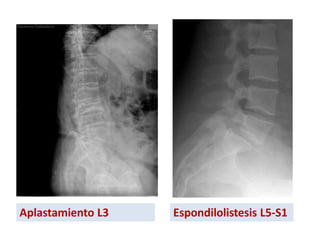

Aplastamiento L3 Espondilolistesis L5-S1

Exploraciones complementarias Radiología simple ✓La evolución natural de la lumbalgia es hacia la resolución espontánea en unas 4-6 semanas. Por ello, en la mayoría de los pacientes (aquellos sin signos de alerta) no estará indicado ningún estudio radiológico (grado de recomendación A), ✓ La anamnesis y la exploración física bastará para orientar y tratar una lumbalgia. ✓ La mayor utilidad de la radiografía simple de columna lumbar, en proyección lateral, es la sospecha de fractura vertebral (grado de recomendación B). No hay que olvidar que el grado de irradiación de una radiología simple de columna lumbar es de, aproximadamente, la de unas 50 radiografías de tórax. Además, será fácil encontrar alteraciones radiológicas sin valor diagnóstico (signos degenerativos, escoliosis, cifosis, hiperlordosis, anomalías de transición lumbosacra, espondilolistesis, etc).